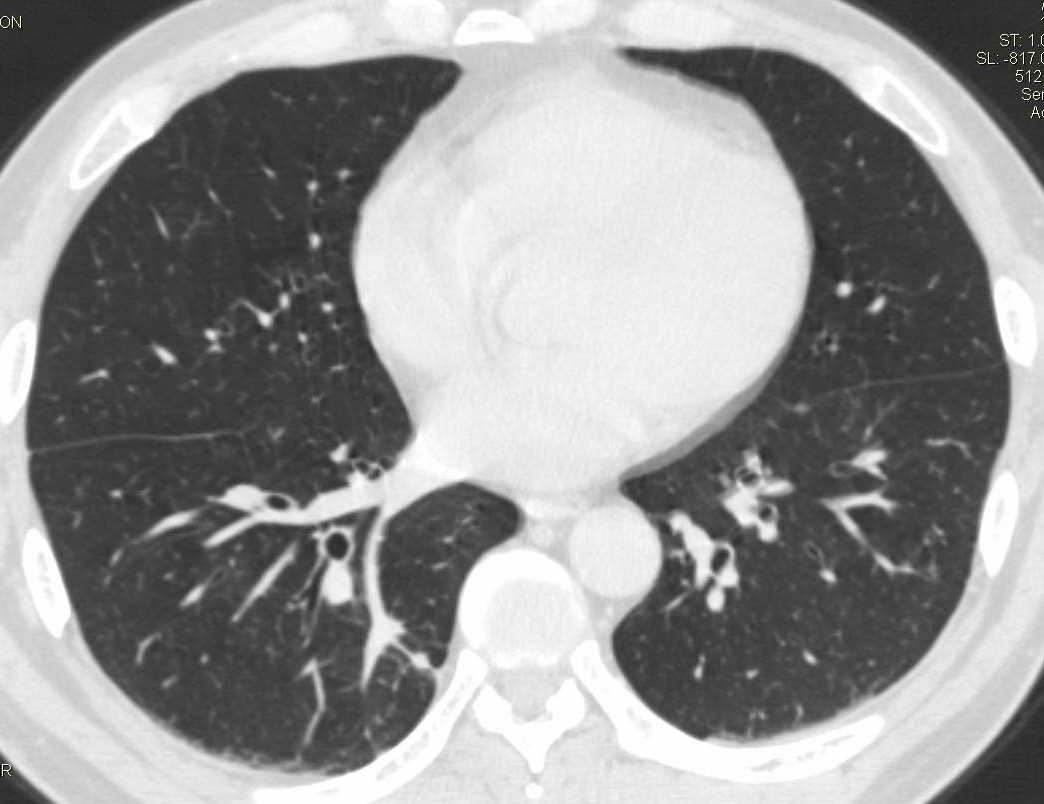

两肺下叶肺纹理增多、增粗并呈“树芽状”改变。支气管扩张呈囊状,部分呈柱状改变。其周围可见散在的斑片样及条索样密度增高影,右肺下叶近叶间胸膜可见一形态不规则的高密度结节影,并与胸膜粘连。

考虑:支扩并发感染。

双肺间质性改变(间质纤维化?)伴支扩。右肺下叶有毛刺的小结节,考虑周围型肺癌可能性。